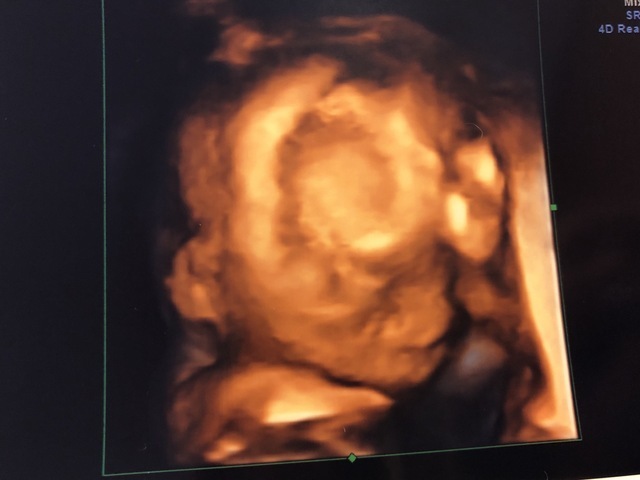

19週1日(19w1d・男の子)|きうらよしこ さん(35歳)

エコー写真撮影時のエピソード:

初めて4Dエコーで我が子を見ることができました。普通のエコーに比べ、鮮明に顔を見ることができ、更に愛しく思えたのを記憶しています。悪阻がきつかったですが、時折写真を眺め、悪阻があるってことは子どもが元気に育っている証拠なんだなぁ等気持ちが前向きになり、どんなお顔なのかな?等話しかけたりしていました。主人も写真を見返しては、どっちに似てるんだろうなぁと嬉しそうに話していました。食事面に関しては、幸い食べ物は何でも食べれたので、あまり神経質にならず好きなものを口にしていました。ですが、出来るだけ自炊をし、赤ちゃんに良いものをと色々ネットで調べて作ったりしました。自分が口にしたものがそのまま我が子へ繋がってるんだなぁ、しっかり栄養とってね等話しかけたりもしてましたね。